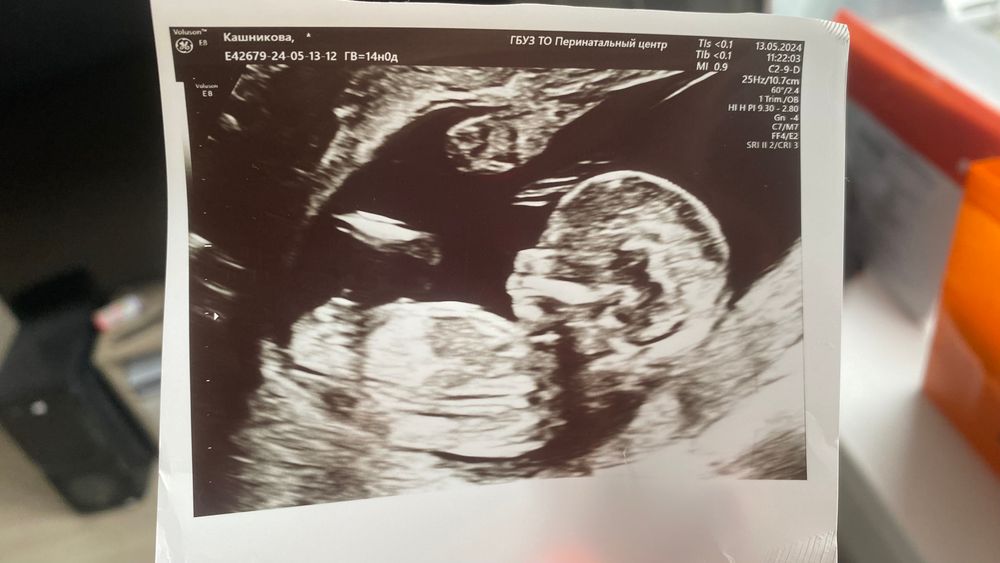

Мальчик или девочка? Первое узи

Недавно была на первом узи ( 14 недель по М, по узи 13,3). И вот безумно интересно кто же живет в животике. Как вы думаете?